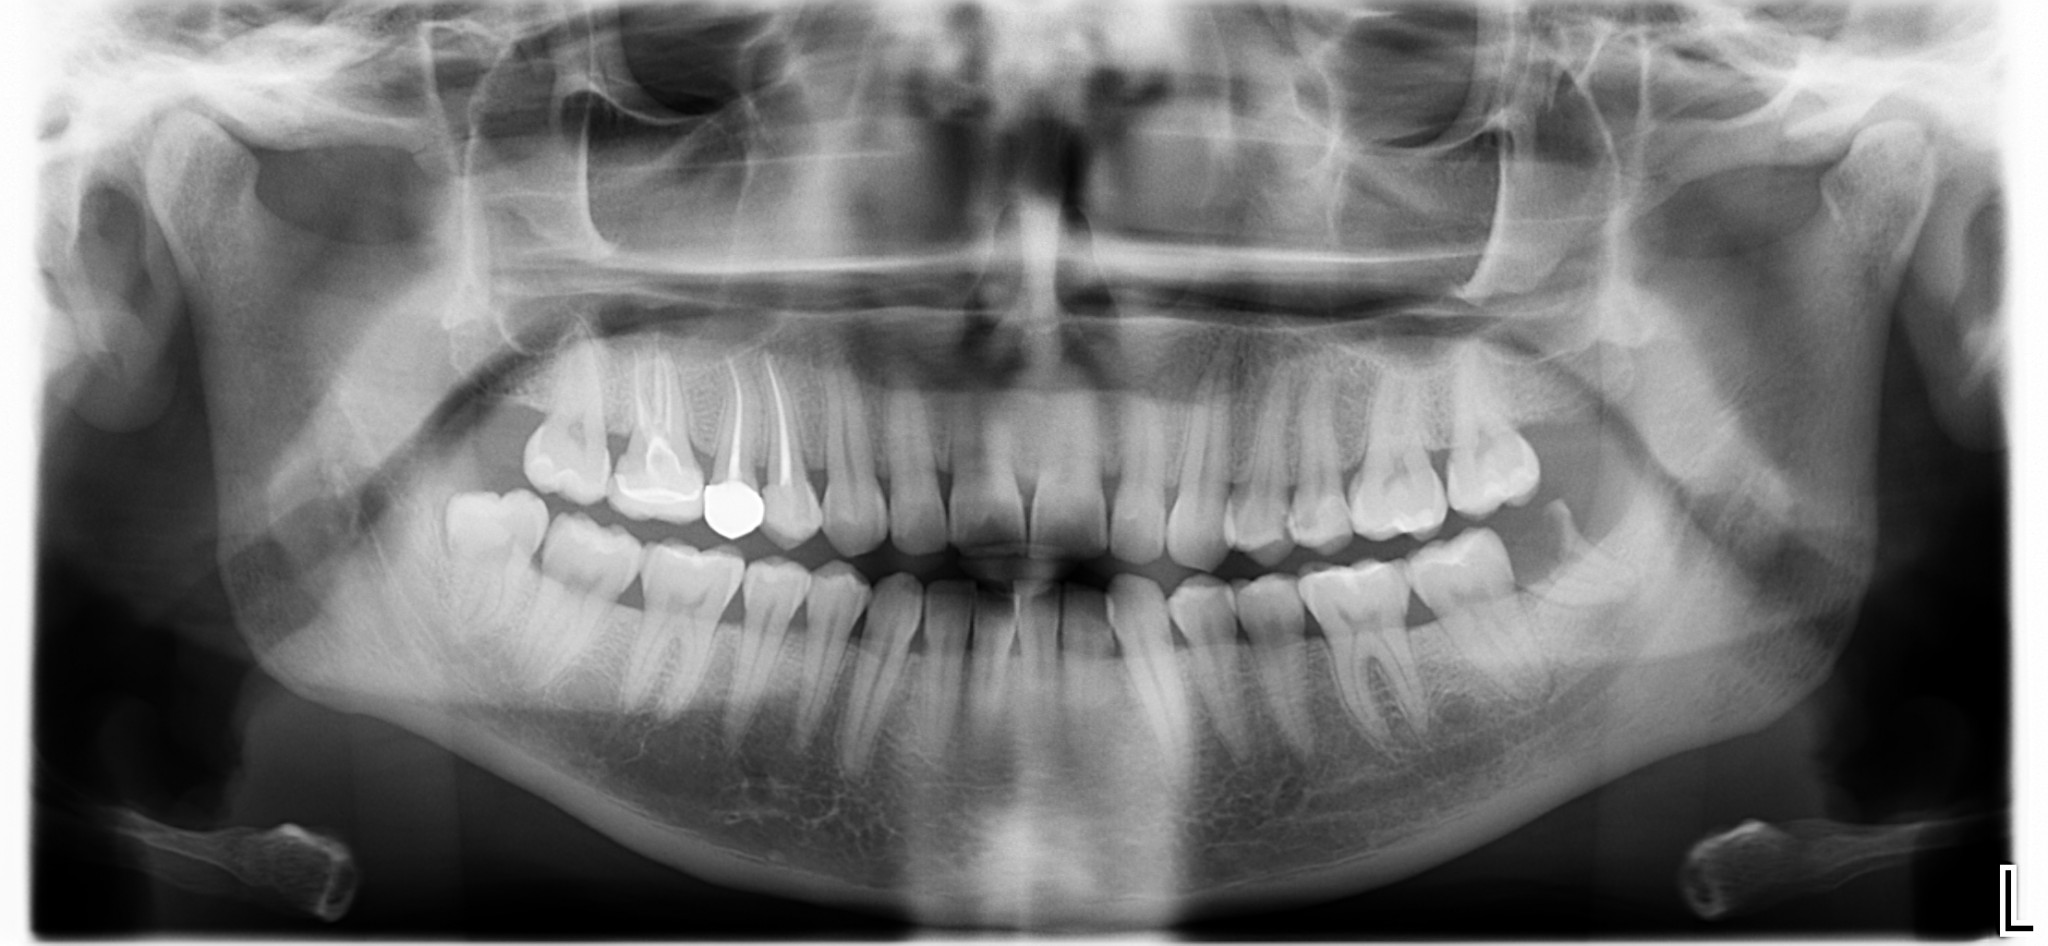

Per la quarta volta in due anni Angelica aveva male al 38. Un male da sbattere la testa contro il muro ma inspiegabilmente non lo aveva ancora tolto.

Ma ora torniamo alla mia esperienza odierna. In realtà Angelica mi ha raccontato che il vecchio dentista aveva provato a togliere il dente ma questo si era “rotto” durante l’estrazione e a quel punto è iniziata l’avventura.

“Il dentista mi ha detto che era un bel casino… avrebbe dovuto tagliarmi, “bucarmi” l’osso e poi darmi i punti. Avremmo dovuto farlo un’altra volta perché, appunto, era un bel casino. IO SONO ANDATA IN PALLA E NON MI HA PIU’ VISTO”

Dopo dieci minuti da questo mio pensiero quello che restava del dente aveva abbandonato la bocca di Angelica e giaceva sul mio carrello chirurgico.

Accettando il fatto che le complicazioni operative succedono e ipotizzando che il collega possa aver avuto un buon motivo per non riuscire in prima seduta a togliere quel dente ?, perché io in dieci minuti ho tolto il dente alla povera Angelica mentre il collega non ci è riuscito in due anni?